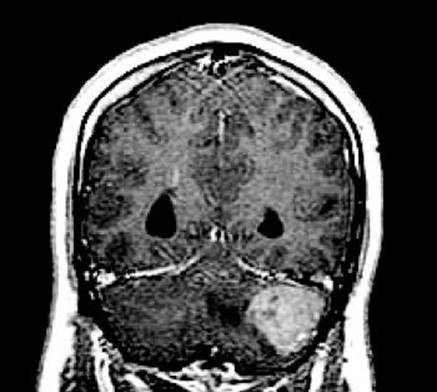

Patients generally present with a combination of altered mental status and focal neurologic symptoms. Neurologic deficits often progress rapidly and the diagnosis is usually made within 2 to 3 months. Seizures are less common than among patients with gliomas. PCNSL has a predilection for arising in deep or midline brain structures. On MRI scans, PCNSL characteristically appears as a bright fairly homogeneously enhancing mass lesion (Fig. 52.4). About one-half of patients have multifocal lesions. Lymphomatous infiltration of the posterior vitreous and/or retina (often asymptomatic) occurs in 10% to 20% of patients. Leptomeningeal dissemination occurs at some time in 10% to 40% of patients and is usually asymptomatic when present at the time of initial diagnosis.

FIGURE 52.4 Coronal T1-weighted MRI scan from a patient with PCNSL, showing a large area of bright homogeneously enhancing tumor centered in the left thalamus, and a smaller focus of enhancing tumor in the superficial right frontal lobe.